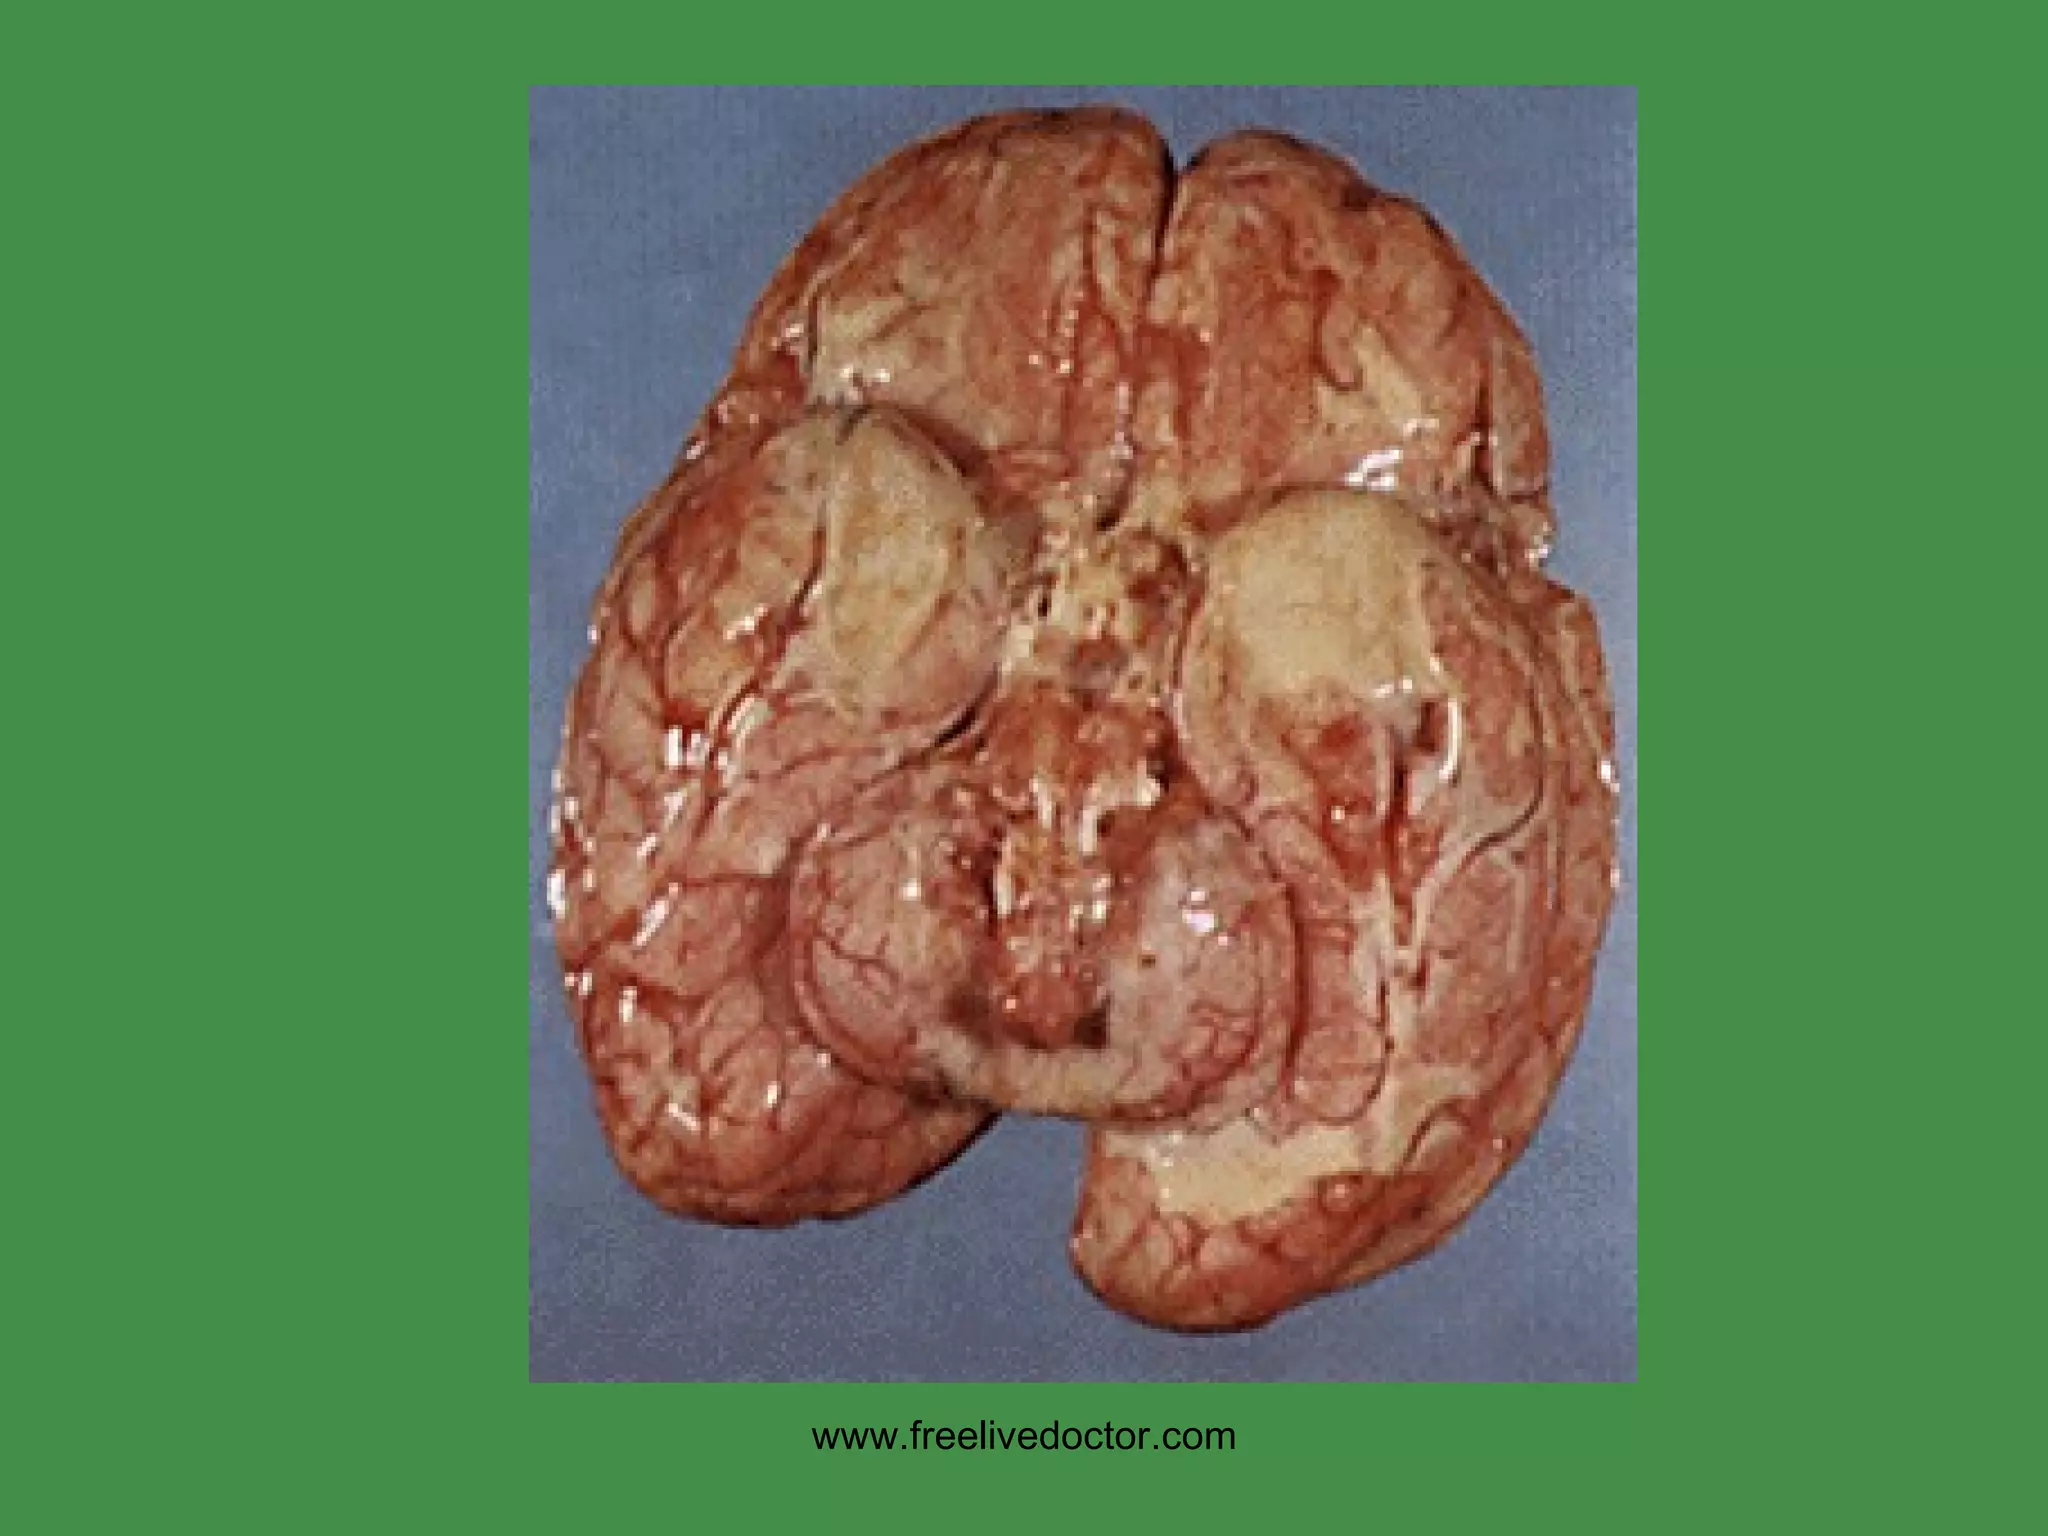

METASTATIC CNS TUMORS LUNG BREAST MELANOMA KIDNEY GI www.freelivedoctor.com

• #163 Note cortical compression from this meningioma.

• #166 A solitary brain mass is statistically just as likely to be metastatic than primary